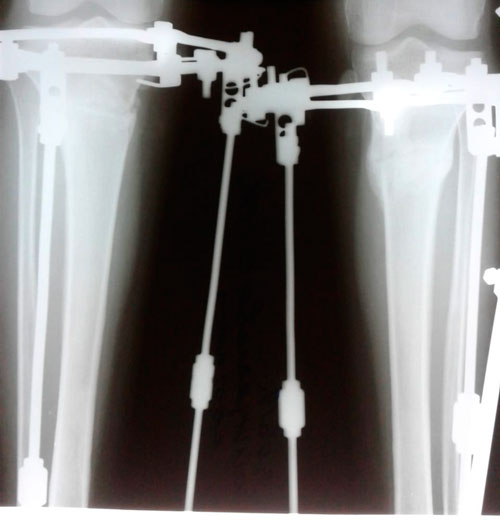

Дата операции - 04.03.2019г.

Дата снятия аппаратов - 03.06.2019г.

Срок сращения - 90 дней.